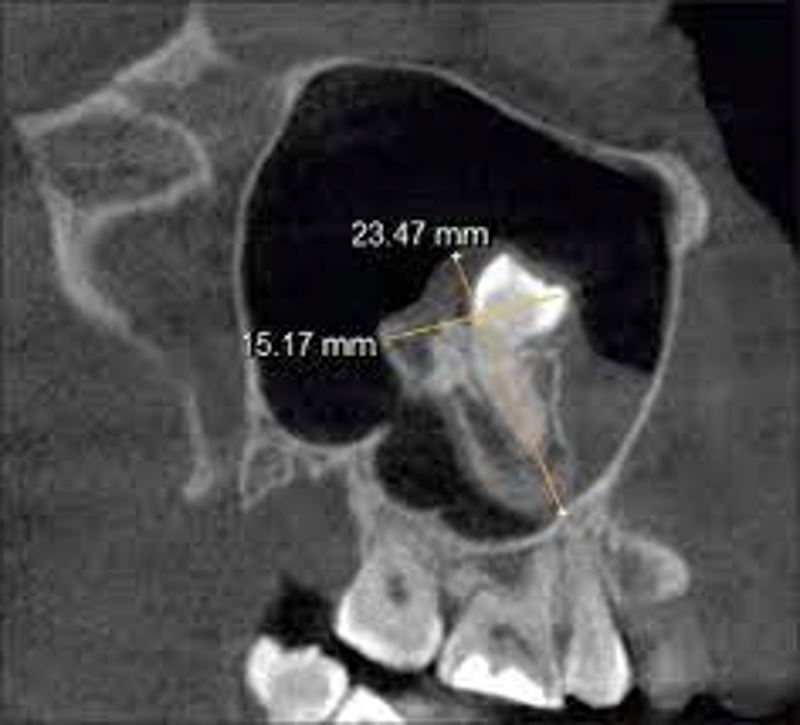

A CT scan revealed the startling diagnosis: a tooth growing inside the nasal cavity.

Medically, the man had an “inverted ectopic tooth” which developed in his nose. Ectopic teeth are when teeth grow in the wrong places which are extremely rare.

man had trouble breathing, doctors found teeth growing in his nosePhoto via Indian Journal of Dental Research